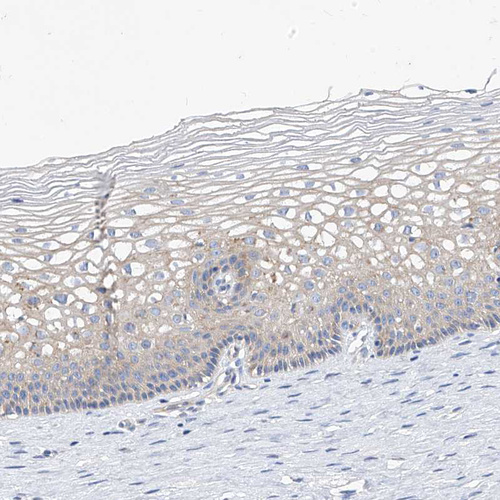

Immunohistochemistry analysis in human cervix, uterine and lymph node tissues using HPA034584 antibody. Corresponding SCGB2A1 RNA-seq data are presented for the same tissues.